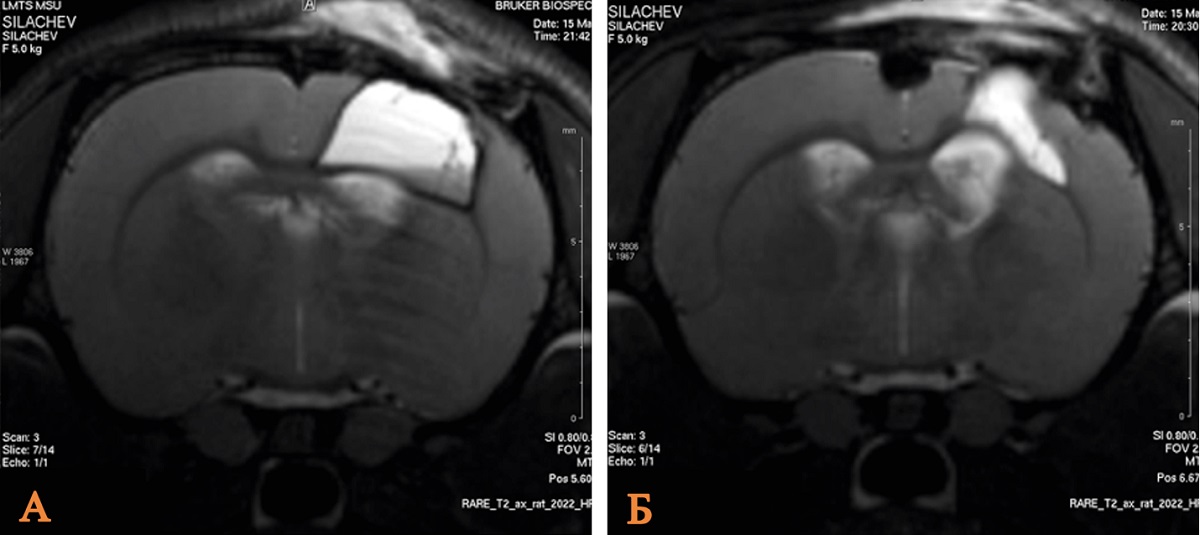

Traumatic brain injury is a primary cause of death and disability, with significant physical, social and economic effects. The study of neuroprotective properties of pharmacological drugs is an important scientific task. Comparison of the lithium chloride effect in the doses of 63 mg/kg and 21 mg/kg after 60 and 180 minutes in open traumatic brain injury experimental modeling in rats is the research aim. Male Wistar rats (n = 60) are included in the study: control group, sham-operated animals and four groups depending on the administered dose of lithium chloride and time intervals. On day 14 after traumatic brain injury, magnetic resonance imaging is utilized to examine the extent of brain damage in rats. Comparative analysis of lithium chloride’s effect on brain damage severity across the studied groups indicates that a 63 mg/kg dose, administered 60 minutes post-injury, demonstrates optimal efficacy in the traumatic brain injury model.